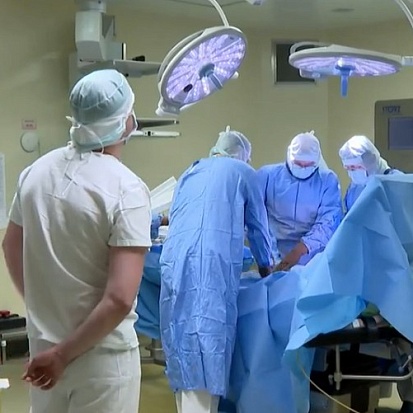

Тестирование роботической системы